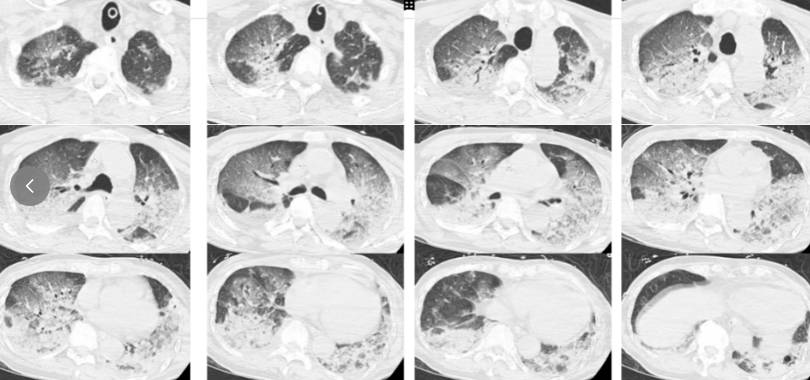

2024年12月,浙江杭州,酷爱蒸桑拿的韩爷爷(化名)于午饭后前往洗浴中心。不料刚进去没多久,整个人就昏了过去并口吐白沫,周围人帮忙拨打了120,将他送入医院。入院时,韩爷爷意识不清,血压、心率下降,医生随即为他安排头颅、胸部CT和肺血管CTA检查,结果显示,老人的双肺出现大面积白色影像。经会诊,韩爷爷被确诊为热射病诱发的肺水肿。 风险场景一 密闭的暖气房、温泉池或汗蒸室:冬季室内供暖后,尤其是北方地区,室温常维持在25℃以上。若长时间处于这种温暖、干燥且不通风的环境中,体温调节能力较弱、对温度不敏感人群可能在无意识状态下脱水,进而引发隐性体温升高。 风险场景二 穿着过于紧身的衣服高强度运动:冬季进行剧烈运动(如马拉松、高强度健身房训练)时,人体产生的热量会剧增。若穿着过于厚重、透气性差的衣物,汗水无法蒸发,在体表形成“保温层”,会严重阻碍散热。运动结束后,若未能及时擦干汗水、更换干爽衣物,且继续停留在温度较高的室内,患病风险同样会显著上升。 哪些人群需格外警惕? 部分老年人因身体机能衰退,对高温及口渴的感知能力显著下降; 部分神经系统疾病患者(如帕金森病、脑卒中后遗症),其体温调节中枢受损; 长期服用特定药物(如抗胆碱能药物、利尿剂、精神类药物)人群,排汗和体温调节功能会受到影响; 儿童体温调节能力差、代谢快、产热多、表达能力有限。 即便在看似舒适的室温下久坐、睡眠,上述人群也可能不知不觉中出现体内热量蓄积的情况。 不慎“中招”怎么办? 可通过三步紧急处理方法来解决: 1. 脱离环境 迅速让患者脱离高温、高湿环境,将其转移至通风阴凉处。 2. 持续降温 持续对患者采取降温措施,如冷水擦拭皮肤、冰敷等。 3. 防止误吸 当患者陷入昏迷,应将其头偏向一侧,保持呼吸道通畅,及时清除气道内分泌物,防止误吸。 热射病是体内热量“暴动” 冬季的“暖”也可能悄然致病 防范热射病 应打破季节思维定式 若冬季出现不明原因高热、昏迷 应警惕热射病风险 来源:国家应急科普宣传 编辑:张艺 |